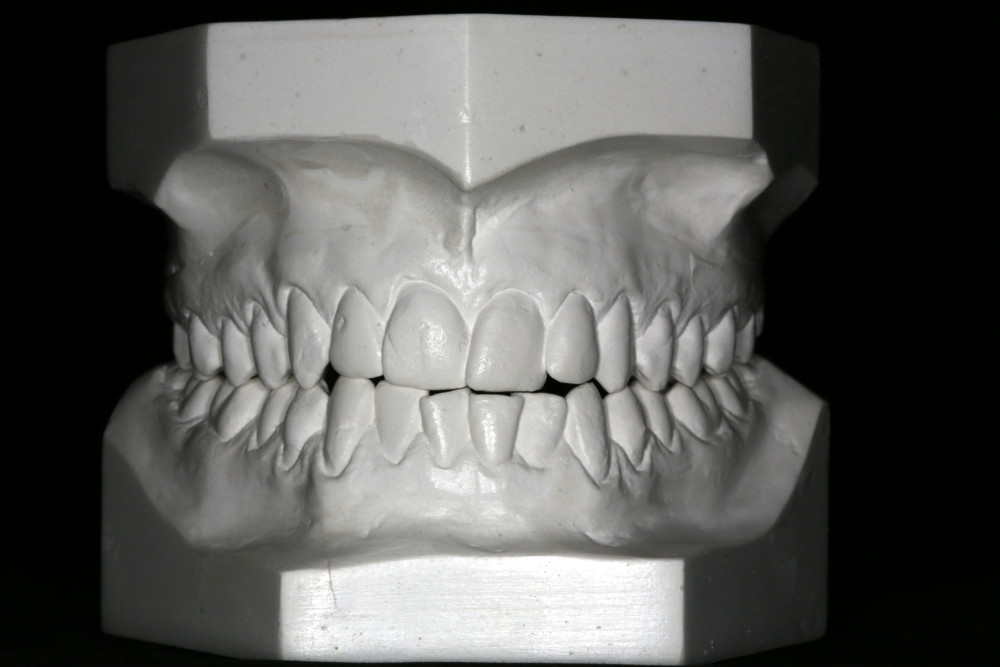

Przykład ekstruzji ortodontycznej za pomocą płytki termoformowalnej i zameczka ortodontycznego: